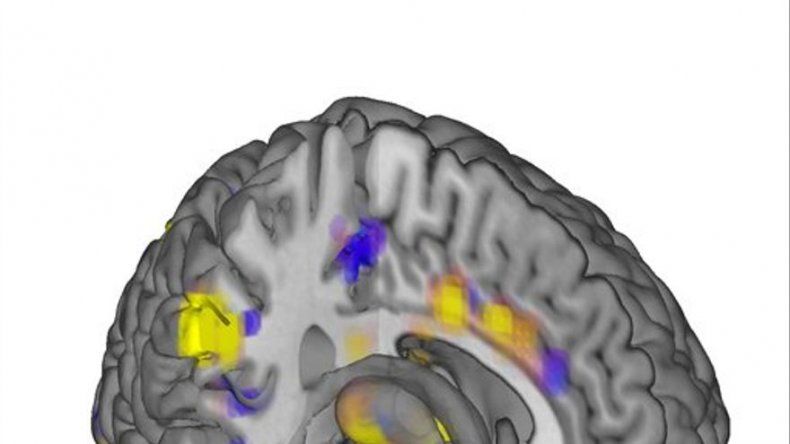

Aunque muchos estudios han localizado zonas cerebrales que se iluminan ante la presencia del dolor, el nuevo trabajo es el primero en desarrollar un indicador que combina todas esas señales que pueden utilizarse para medir el dolor.

Se utilizaron imágenes de resonancia magnética funcional _que no requieren radiación como los rayos X_, las cuales registraron cambios en la actividad cerebral medidos en base al flujo de sangre. Varias computadoras generaron marcas o patrones a partir de esas lecturas.